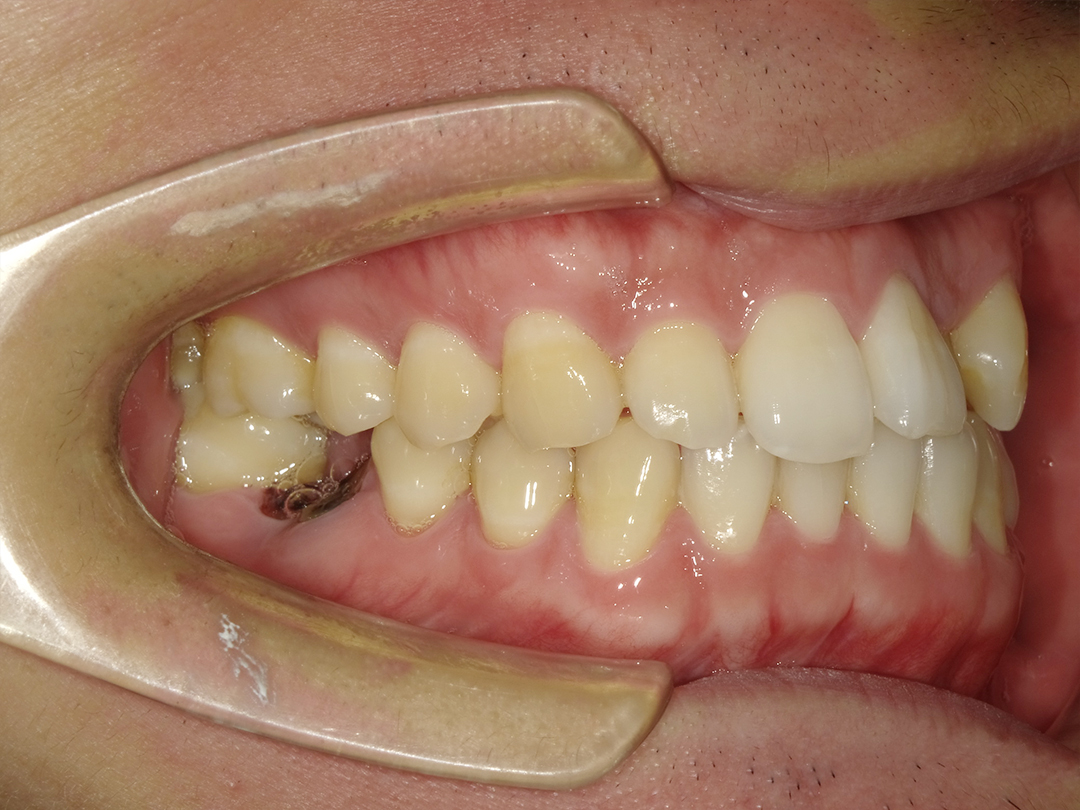

ALL ON全口重建是由4-6 顆植體(依條件而定)成,專為多顆缺牙或全口無牙患者設計的創新全口重建技術,僅需4-6 支植體即可支撐一整排固定式假牙,大幅減少手術次數與成本,並縮短療程時間。

適用無牙或重度牙周病患者

免補骨/少補骨即可植牙,降低手術複雜度